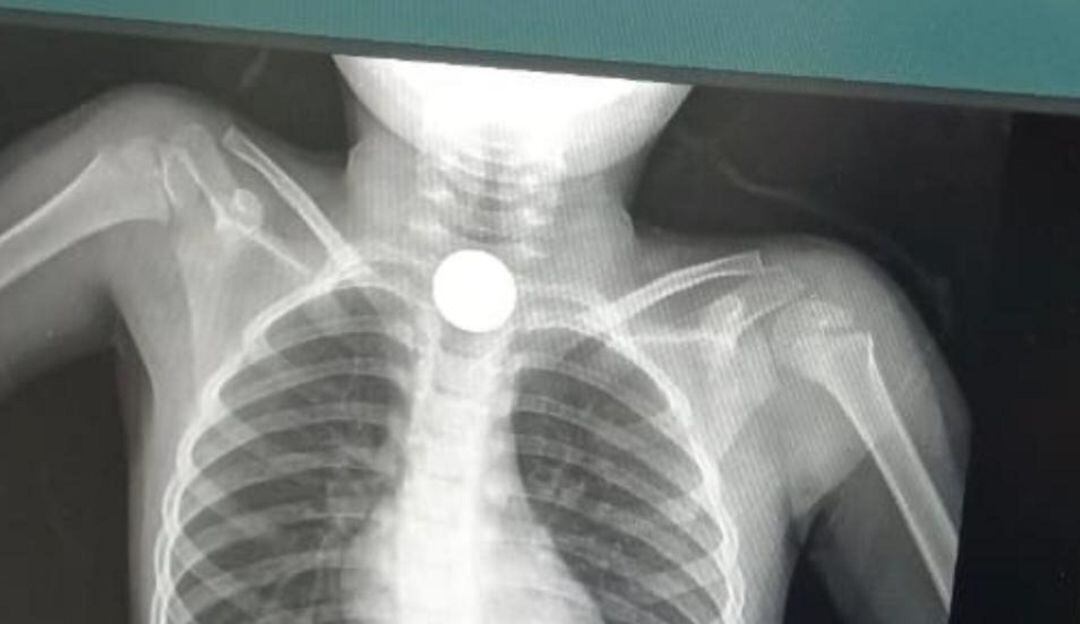

Placa del menor. / Cortesía

Un campesino de la Sierra Nevada denuncia que, a su hijo de seis años, quien de manera accidental se tragó dos monedas y la tiene atascada en su garganta, no le brindan atención urgente en una clínica de Santa Marta.